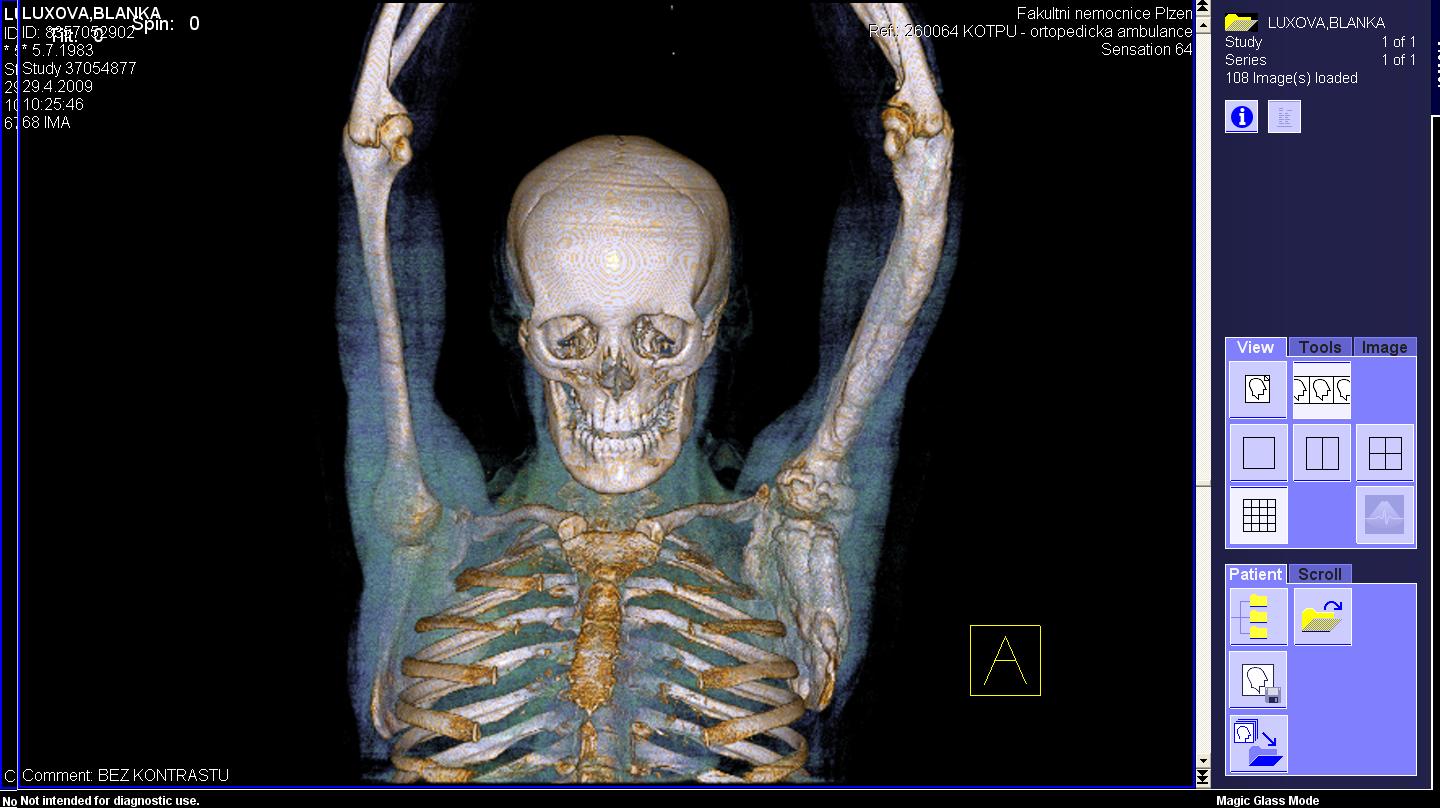

Area(s) affected:  Left arm and hand

I am sending you some photos from RTG and CT and scinti scam from last month.